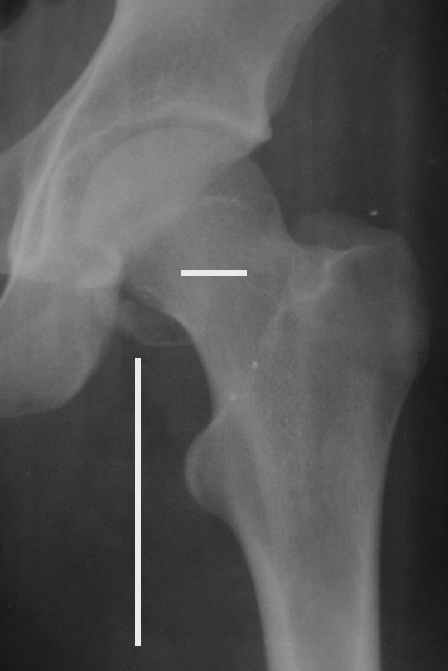

Уважаемые коллеги! Заканчивая обследование больного с переломо-вывихом бедра сделал ему обычные R-томограммы. Кажется удалось "поймать" и отломок и донорское место. Мои выводы - в скиаграмме. Считаю, что это передне-нижний фрагмент головки, образовавшийся вследствии отрывного перелома. На томограммах отломок обозначаю длинной стрелкой, а место откуда он оторвался - более короткой. Учитывая тот факт, что его размеры по КТ 25 х 15 мм считаю, что его фиксация на место необходима для профилактики артроза, что при 16-ти летнем возрасте пациента важно в плане максимального отодвигания эндопротезирования. Планирую оперировать его 24.05.05 г. Результаты представлю.

Прямой 19.05

Несколько соображений к "картинкам". На прямом снимке и КТ-томограммах все типичные линии вертлужной впадины: крыша, передняя стенка, задняя стенка - сохранены. На КТ-сканах 6 и 7 появляется фрагментация головки. С учетом R-томограмм отломок расположен спереди-снизу, а не сзади-сверху от сустава, как написано в описании КТ.